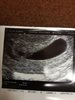

Gratulację!! Piękny bobabsek :) A powiedz proszę czy lekarz zwrócił uwagę na pęcherzy? Bo widzę że jest dość duży, mój też jest ogromny i trochę mnie to martwi. Lekarz mówił że to nic takiego ale też dodał że inny lekarz by dał pewnie jakieś leki ale on uważa że jest ok. No więc dał mi trochę tym do myślenia.

• 25552635_1703333526394972_615523694_o.jpg

25552635_1703333526394972_615523694_o.jpg

188,9 KB · Wyświetleń: 704

Hej,

USG z 5t1d, dzis mija nam 7:) Kropeczka miala wtedy 2,2mm, pęcherzyk prawie 9mm. Dziewczyny, jak u Was z dolegliwosciami? U mnie tragedia... Nudnosci, piersi, ciagle pragnienie itp itd...